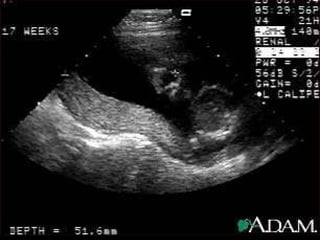

Líquido Amniótico No início da gestação o volume de L.A. supera o volume do concepto. No 2º e 3º trimestre a maior fonte de produção é o rim fetal. A termo, o volume corresponde a 600ml (volume máximo - 38 semanas) Deglutição fetal, vias urinárias e movimentos respiratórios. Proteção (água,eletrólitos,glicose,lipídeos, proteínas, células…)

Líquido Amniótico Noinício da gestação o volume de L.A. supera o volume do concepto. No 2º e 3º trimestre a maior fonte de produção é o rim fetal. A termo, o volume corresponde a 600ml (volume máximo - 38 semanas) Deglutição fetal, vias urinárias e movimentos respiratórios. Proteção (água,eletrólitos,glicose,lipídeos, proteínas, células…)